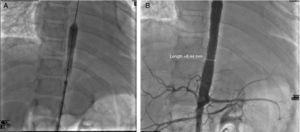

A computed tomography scan revealed hypoplasia of the right vertebral artery (V4), left subclavian stenosis and narrowing of the descending aorta with arteritis data on the wall, yuxtadiafragmática and transverse diameters of 4.5–5.0mm. Were also stenosis in the origin of the superior mesenteric artery (3.3mm) and significant stenosis in the origin of the right renal artery (Fig. 1).

The diagnosis of TA III was based on the following: decreased peripheral arterial pulses and limb claudication, pressure difference greater than 10mmHg, murmur over the aorta, arterial hypertension and angiographic abnormalities (thoracic ascending and abdominal aorta and renal arteries).